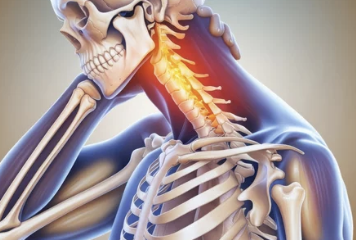

목디스크(경추 추간판 탈출증)는 목뼈 사이에 있는 디스크(추간판)가 탈출하거나 찢어져 신경을 압박하는 상태를 말합니다. 이로 인해 통증, 저림, 움직임 제한 등이 발생합니다.